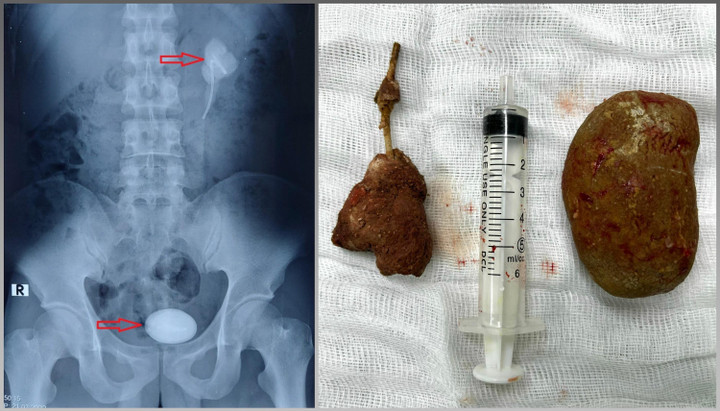

Hình ảnh hai viên sỏi.

Kết quả siêu âm và chụp cắt lớp vi tính hệ niệu ghi nhận thận trái của bệnh nhân ứ nước độ II, sỏi vùng bể thận - niệu quản bên trái, kích thước 30x58mm, sỏi bàng quang kích thước 90x58mm, có 1 đoạn ống thông JJ trong cả 2 viên sỏi.

Sau 3 giờ phẫu thuật, các bác sĩ đã lấy thành công 2 viên sỏi với trọng lượng 300g ra khỏi cơ thể bệnh nhân.